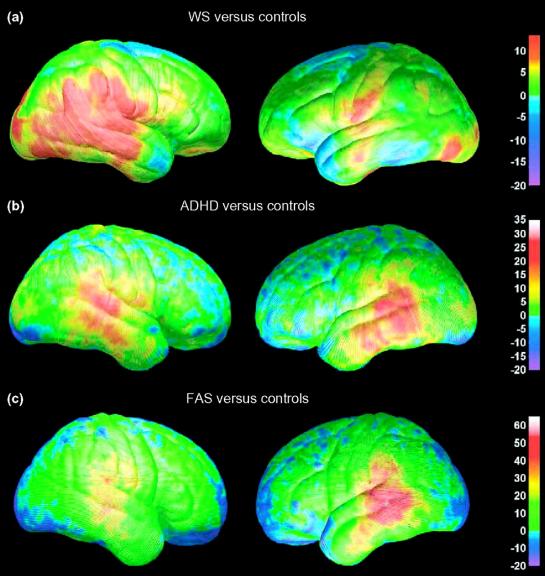

ADHD Brain Vs Normal Brain Functions Differences More

ADHD Brain Differences Stuff4Educators

ADD ADHD Program Dr Zembroski

Adhd Vs Normal Brain Brain Patterns Put Adhd In Focus Australasian

Brain Markers Of ADHD Identified In Children s MRI Scans